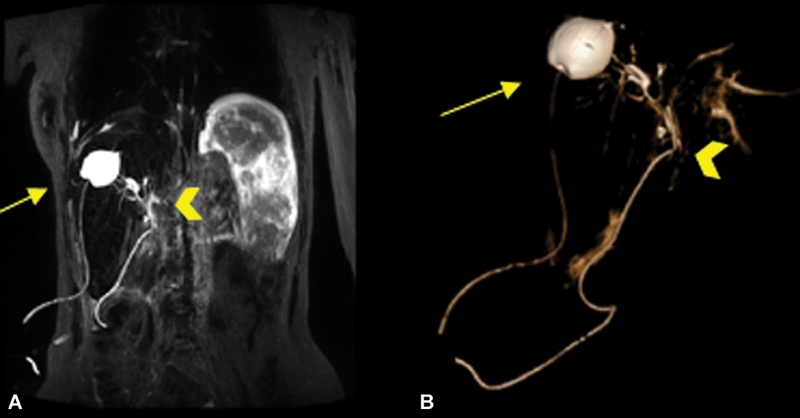

Concurrent rupture of hepatic hydatid cysts into the biliary tree and into the pleural cavity is a very rare complication in echinococcosis and can pose diagnostic and treatment challenges. We present the case of a 15-year-old female patient with recurrent abdominal pain, chest pain, fever, vomiting, jaundice, and cholangitis. Ultrasound, X-rays, computed tomography of the abdomen and thorax and cholangio-magnetic resonance imaging revealed a hepatic hydatid cyst with rupture into the main biliary duct causing obstruction, gallbladder microlithiasis, rupture of the right hemidiaphragm, and pleural hydatidosis. Echinococcus serology tests were positive. Endoscopic retrograde cholangiopancreatography (ERCP) could not resolve the obstructive jaundice. A laparotomy with choledochotomy, removal of hydatid structures, choledochal drainage with Kehr tube, cholecystectomy, Lagrot partial pericystectomy, partial pleural resection, suturing of the diaphragm, and triple drainage (right pleural cavity, cystic cavity, and Douglas pouch) was performed. Perioperative albendazole and antibiotic therapy was administered. The patient had an uneventful postoperative course. Follow-up at 1, 6, 12, and 24 months showed a favorable evolution without relapse of the hydatidosis. The very rare complications of cholangiohydatidosis and concomitant hepatothoracic transit lead to a severe condition, which needs adequate surgical treatment. Clinical presentation and laboratory findings are not specific and may simulate an obstructive jaundice and acute cholangitis of other etiology. ERCP with endoscopic papillotomy offers the advantage of a minimally invasive surgery, but it does not allow a definitive treatment of the whole problem and may be useful as a bridge procedure to drain the bile duct while awaiting definitive surgery.